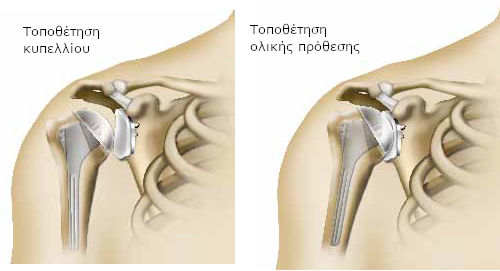

Ανάλογα με την περίπτωση, είναι δυνατό να αντικατασταθεί είτε μόνο η κεφαλή του βραχιονίου ( πρόθεση βραχιόνιας κεφαλής), είτε και τα δύο μέρη της άρθρωσης, δηλαδή η κεφαλή του βραχιονίου και η ωμογλήνη (ολική πρόθεση).

Εάν αντικατασταθεί μόνο η κεφαλή του βραχιονίου, μιλάγε για πρόθεση βραχιόνιας κεφαλής. Αποτελείται από το στέλεχος της πρόθεσης (στυλεός), το οποίο εισάγεται στο βραχιόνιο. Στο στέλεχος εφαρμόζει ένα τμήμα, ανάλογης μορφής με την κεφαλή του βραχιονίου (η κεφαλή πρόθεσης).

Εάν αντικατασταθεί και η ωμογλήνη, μιλάμε για ολική πρόθεση. Εκτός από τα τμήματα που έχουν τοποθετηθεί στο βραχιόνιο, προστίθεται ένα ακόμα μέρος που ονομάζεται κυπέλλιο και τοποθετείται στη θέση της ωμογλήνης.